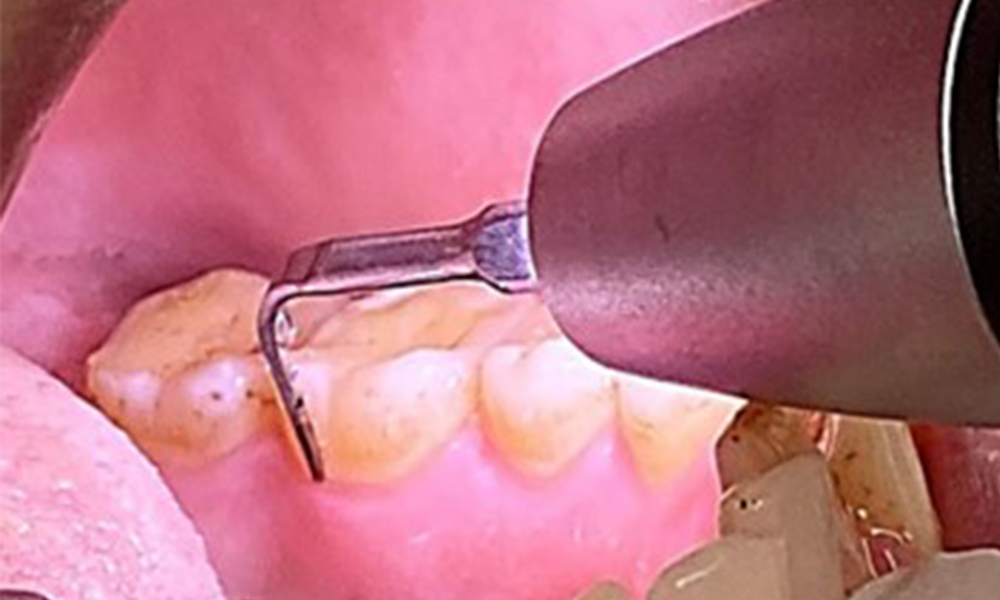

Aufgrund des guten allgemeinmedizinischen Zustandes ist der aus der Mundgesundheit ermittelte Bedarf maßgebend für die Behandlung. Die regelmäßige Erhebung der Sondierungstiefen ist unabdingbar. Die gingivale Blutung ist bei Rauchern herabgesetzt, weswegen die klinische

Diagnose einer Parodontitis nur durch Sondierung möglich ist (Abb. 7). Die ausschließliche Erhebung von Blutungsindizes verdecken unter Umständen das Bild einer bestehenden Parodontitis oder Gingivitis. (5)

Taschensondierung (BOP) mit Darstellung der Rg. 36 lingual

Abb. 7 Taschensondierung (BOP) mit Darstellung der Rg. 36 lingual, © Dr. R. Krapf